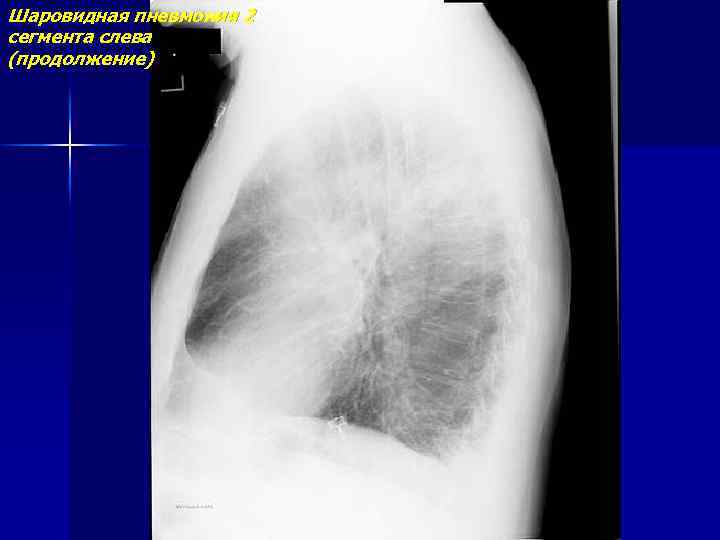

Шаровидная пневмония 2 сегмента слева

Шаровидная пневмония 2 сегмента слева (продолжение)